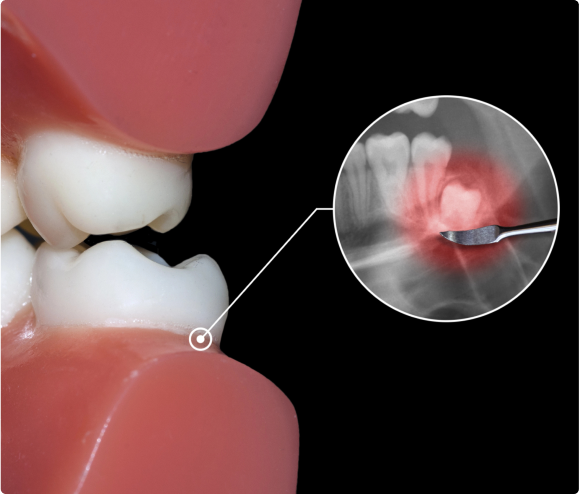

• Wisdom teeth also can be impacted, which means they become enclosed within the soft tissue and/or the jawbone or only partially break through or erupt through the gum. Partial eruption of the wisdom teeth allows an opening for bacteria to enter around the tooth and cause an infection, which can cause pain, swelling, jaw stiffness, and general illness. Partially erupted teeth are also more prone to tooth decay and gum disease because their difficult-to-reach location and awkward positioning make brushing and flossing difficult.

• The relative ease with which a dentist or oral surgeon can extract wisdom teeth depends on the position of the teeth and their stage of development. A wisdom tooth that has fully erupted through the gum can be extracted as easily as any other tooth. However, a wisdom tooth that is underneath the gums and embedded in the jawbone will require an incision into the gums and then removal of the portion of bone that lies over the tooth. In such cases, the tooth may be extracted in small sections rather than removed in one piece. This minimizes the amount of bone that needs to be removed to get the tooth out.